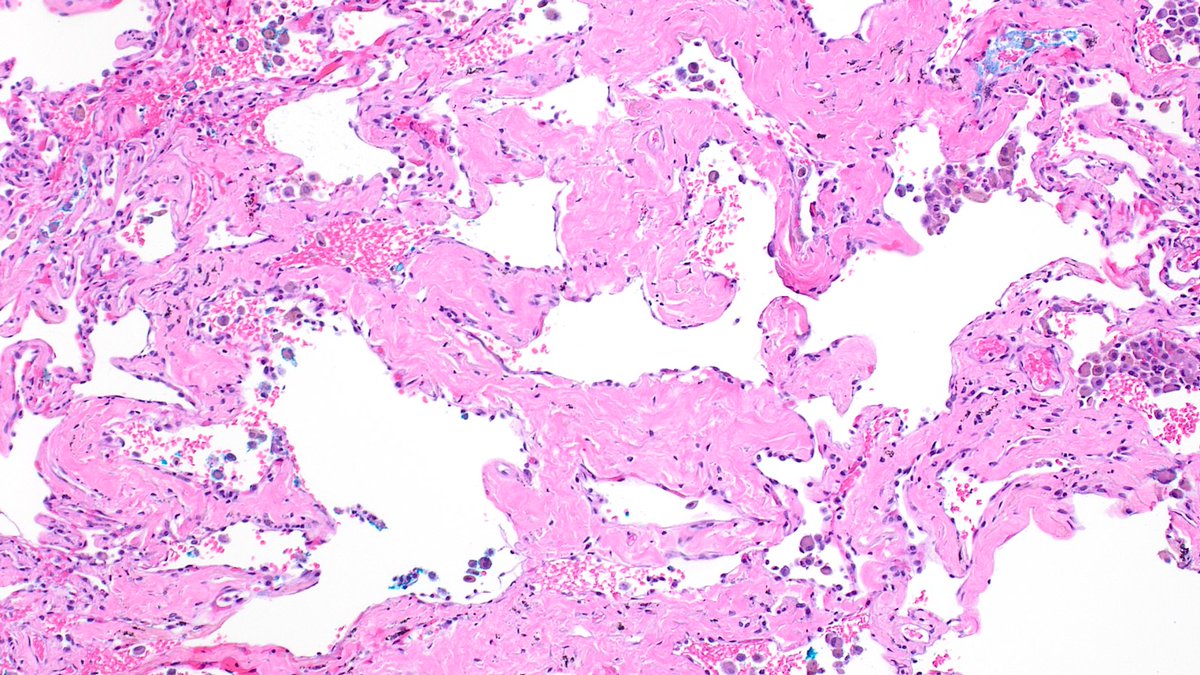

Smoking-related interstitial fibrosis, but if the patient has clinically and radiologically evident interstitial lung disease, clinicians would call this respiratory bronchiolitis with fibrosis interstitial lung disease... so confusing :-0

Interstitial lung diseases are challenging to diagnose. Recently, some terminologies were updated. Read more here: https://t.co/2jHs00zuVz Notably, DIP (now alveolar macrophage pneumonia) and AIP (now idiopathic DAD) are no longer used. #lungpath #lung #moffitt #lungILD